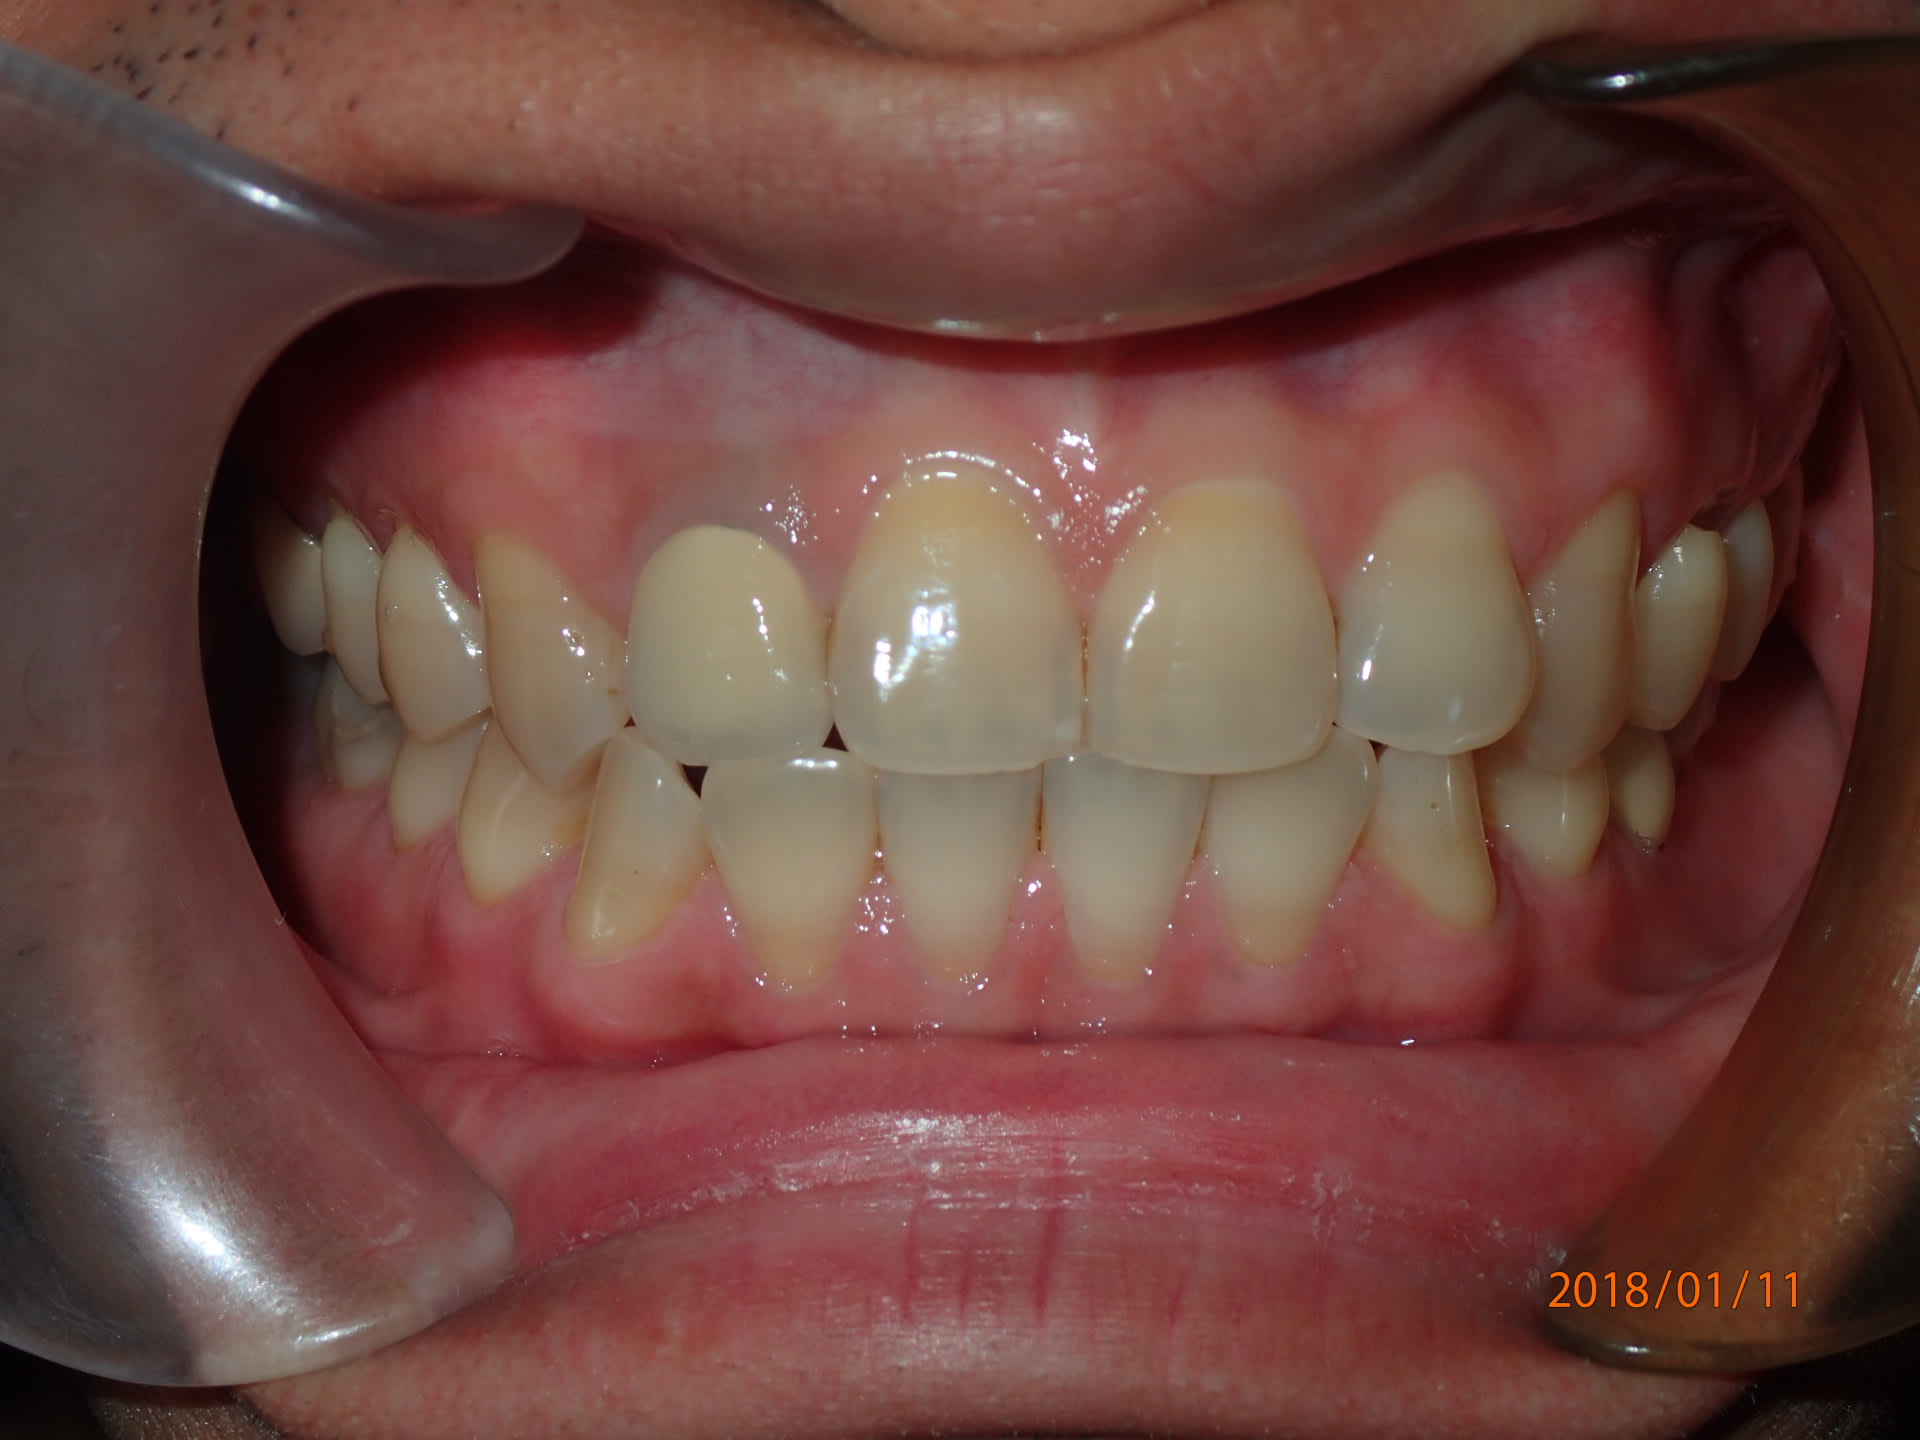

Un petit cas tout simple.

4 mois de traitement, Deux files et pour finir je vais faire deux aligneur sur le set up final ( technique ou l'on fait un aligneur de faible rigidité suivit d'un plus rigide ) .

Cout du matériel bracket/ set up imprimée / aligneur en dessous de 100$ .